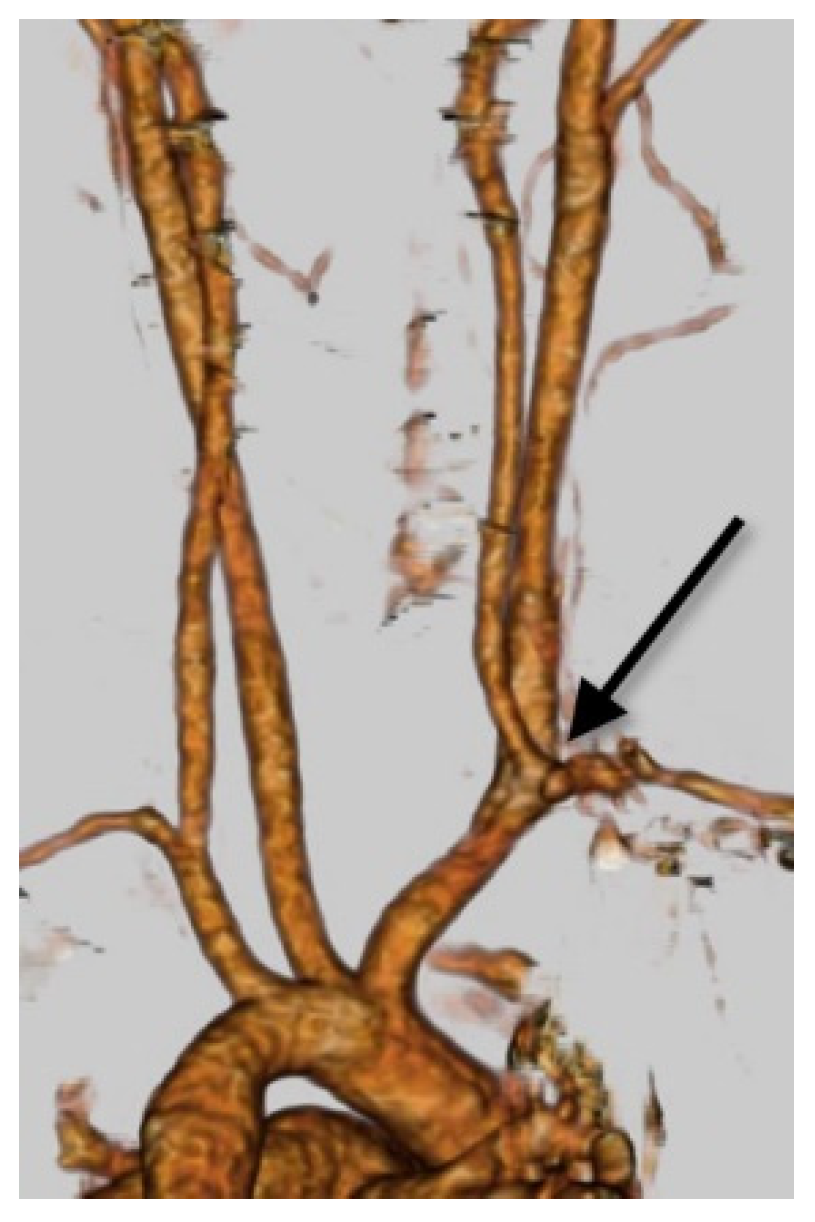

3.3. The Dual Origin of the Right Vertebral Artery